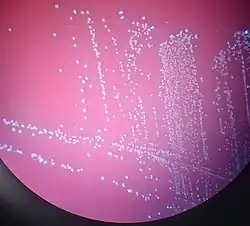

| Aerococcus urinae on blood agar[1] | |

What makes it tricky is that under a microscope, A. urinae shows up as small Gram-positive cocci in clusters or pairs—similar to other bugs we see all the time. On blood agar, it can be alpha-hemolytic or even non-hemolytic, making it even harder to distinguish. In many labs, it was historically brushed off as a contaminant or misidentified entirely.